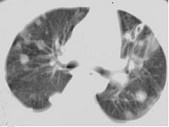

问题 女,32岁,鼻梁双颊部出现红斑伴发热咳嗽2周,肘腕关节游走性疼痛,请结合CT,选择最可能的诊断为 ( )

选项 A.肺部感染 B.结节病 C.肺类风湿病 D.SLE肺部浸润 E.韦格肉芽肿

答案 D